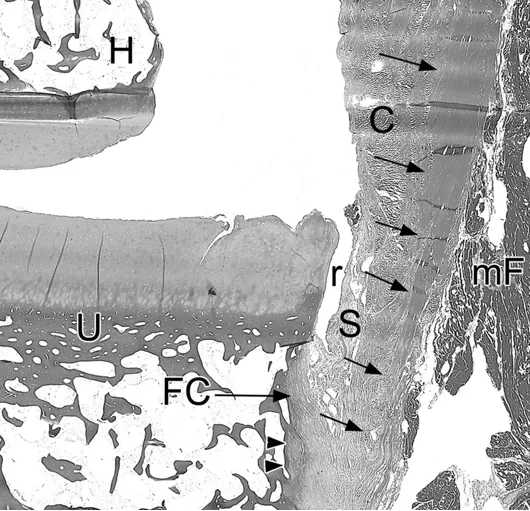

(d)组织学切片照片可见,尺侧副韧带前束(箭所示)附着于尺骨冠状突骨膜,附着点位于关节边缘远侧3毫米处。该韧带前束为单层结构,并与一层存在空泡样变性的纤维软骨(FC)相融合。上述表现符合轻度退行性改变。图中 C 代表关节囊,H 代表肱骨,mF 代表指浅屈肌肌纤维,r 代表滑膜隐窝,S 代表滑膜,U 代表尺骨。